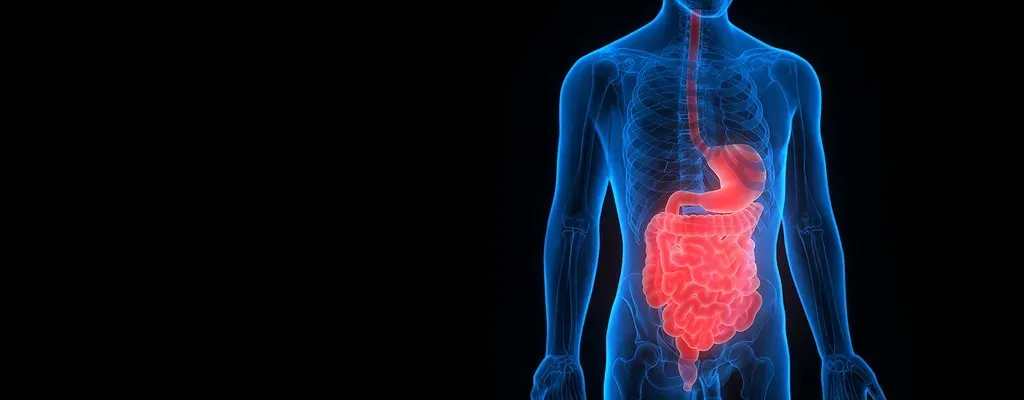

Sign 1: You’re Constantly Bloated – Even After Eating “Healthy” Food

If you regularly experience bloating, gas, abdominal pain, or excessive belching, your microbiome may be struggling. These symptoms often arise when particular gut bacteria overproduce gas from undigested carbohydrates or when the balance of fermenting microbes is disrupted. Honestly, this is one of the most common warning signs people brush off as normal.

Dysbiosis – the loss of beneficial bacteria or the overgrowth of harmful ones – is diagnosed as a decrease in overall gut microbiome diversity, and people in dysbiosis frequently develop symptoms including inflammation of the bowel, diarrhea, food intolerance, gas, and bloating. So that persistent afternoon bloat might not be about what you’re eating. It might be about who’s eating it down there – or rather, who isn’t.

Even when the gut is rich in nutrients, microorganisms can experience nutrient deprivation owing to factors such as fluctuations in host feeding patterns, microbial competition, and selective nutrient uptake by the host. Nutrient starvation affects microbial survival, microbiome dynamics, and intestinal stability, yet remains underexplored. In other words, you could be eating plenty and still have a microbiome that’s functionally starving.

Sign 5: You’ve Developed New Food Sensitivities Out of Nowhere

A food sensitivity is usually delayed and far more subtle than an allergy. Symptoms like bloating, cramps, nausea, headaches, and brain fog can appear hours after eating. These delayed reactions can be related to your microbiome. When beneficial bacteria are reduced, food isn’t broken down properly, leading to fermentation, inflammation, and possible increased sensitivity over time.